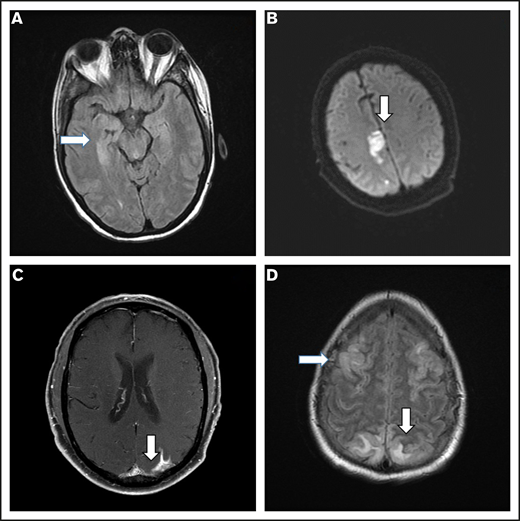

Brain imaging was performed before conditioning therapy in all patients: CT in 83 patients and MRI in 17. Of 68 patients who developed ICANS, 38 had MRIs of the brain at the time of symptoms, 30 of whom had grade ≥3 ICANS. Among the 38 available studies, 5 were negative, 10 were probably negative (evaluation being limited by image quality), 8 showed findings already present before axi-cel infusion, 1 showed nonconclusive findings, and 14 were positive. The most common imaging pattern, observed in 7 patients, was characterized by T2-weighted fluid-attenuated inversion recovery (T2/FLAIR) hyperintensity affecting the limbic system, with or without extralimbic involvement, reminiscent of limbic encephalitis. T2/FLAIR signal change was most often seen, either unilateral or bilateral, in the hippocampus (Figure 2A), insular cortex, thalamus, cingulate gyrus, and the brainstem. All 7 patients had altered mental status (AMS). MRI of brain was repeated in 4 of the patients: in 1 patient, the pattern and symptoms completely resolved 10 days later; in 1 patient with worsening AMS, the imaging findings progressed on multiple scans obtained in the subsequent 20 days; in 2 patients, no change was observed either on neurologic examination or in neuroradiologic findings. The second most common imaging finding was a stroke pattern characterized by focal cortical-based or deep white matter hyperintensity on diffusion-weighted imaging with restricted diffusion (Figure 2B) observed in 3 patients (1 of whom had a known preinfusion diagnosis of atrial fibrillation). All 3 patients presented with AMS. MRI brain was repeated in 2 and showed normal stroke evolution in both. Leptomeningeal enhancement was observed in 2 patients (Figure 2C), 1 of whom had previous CNS disease and was characterized by sulcal enhancement. Both had AMS, and neither had a lumbar puncture nor a repeat imaging study, but corticosteroids induced complete resolution of neurologic symptoms in both patients. Two other patients with AMS had MRI findings consistent with posterior reversible encephalopathy syndrome (PRES; Figure 2D), characterized by posterior bilateral and symmetrical subcortical edema. Repeat imaging in one of the patients showed worsening findings. Among the above-described 14 patients with AMS, 12 had complete resolution of symptoms, 1 with bilateral involvement of the medial temporal lobes died because of status epilepticus on day 51, and 1 with leptomeningeal disease pattern died from progressive lymphoma.

Representative MRI imaging features. (A) Encephalitis (T2/FLAIR axial image). (B) Stroke (diffusion-weighted axial image). (C) Leptomeningeal disease (postcontrast T1-weighted axial image). (D) PRES (T2/FLAIR axial image).

In our study, the most common abnormal finding on MRI was characterized by T2/FLAIR hyperintensity involving parts of the limbic system, typically the hippocampus, thalamus, cingulate gyrus, and extralimbic structures to include the brainstem. Santomasso et al18 reported on 53 patients with B-ALL treated with anti-CD19 CAR T-cell therapy with CD28 costimulatory domain: 33 developed neurotoxicity of any grade, an MRI brain scan was performed in 19, and was abnormal in 5 patients. Similar to what was observed in our study, the most common abnormal finding was hyperintensity of the bilateral thalami and brainstem. Gust et al6 reported findings from 133 patients with B-ALL and B-cell non-Hodgkin lymphoma treated with anti-CD19 CAR T-cell product with 4-1BB costimulatory domain, 53 of whom had neurotoxicity: 23 had an MRI brain scan (mostly patients with severe neurotoxicity), and it was abnormal in 7. The most common finding was cortical swelling and vasogenic edema, prevalent in the basal ganglia, thalami, and brainstem. Although the precise pathophysiology of these MRI findings remains unknown, bilateral involvement of the temporal lobes may be reminiscent of limbic encephalitis, the latter reflecting a general pattern of response to various insults rather than a specific etiology. In this regard, infiltration with inflammatory cells and cytokines have been proposed as a common pathway of brain damage in patients with encephalitis, irrespective of its etiology (autoimmune, paraneoplastic, infectious).19-23

The overlapping radiologic presentation of these different etiologies may support the concept of excitotoxic mechanisms as a potential end pathway to brain injury.24 In this regard, the pattern of involvement on MRI (ie, hippocampi, other limbic structures, and corpus callosum) is in support of the extracellular glutamate excitotoxicity hypothesis, because these locations correlate with increased number of N-methyl-d-aspartate–type glutamate receptors.24 Given its prevalence in our analysis and its consistent report in other studies, this pattern could be CAR T-cell therapy mediated, and functional analysis is warranted to better understand its biologic mechanisms in the contest of cellular therapies, including endothelial dysfunction. In contrast, the other 3 patterns observed (stroke-like, leptomeningeal disease–like, and PRES-like) all represent conditions that may either precede or coexist with axi-cel infusion, and the few cases reported in this study are not sufficient to provide further insights. Systematic evaluation with brain MRIs before CAR T-cell infusion and at time of neurotoxicity onset is needed, to better understand their prevalence and clinical significance.25,26 In addition, consistent CSF assessments at time of neurotoxicity onset may help shed light on their biologic correlates. To this regard, it is unclear whether the stroke-like pattern is reflective of endothelial dysfunction or cardiac arrhythmia. Cytokine-induced endothelial dysfunction could in fact be the primary etiology of multiple imaging patterns, as suggested by vascular and metabolic studies recently reported in these patients.10